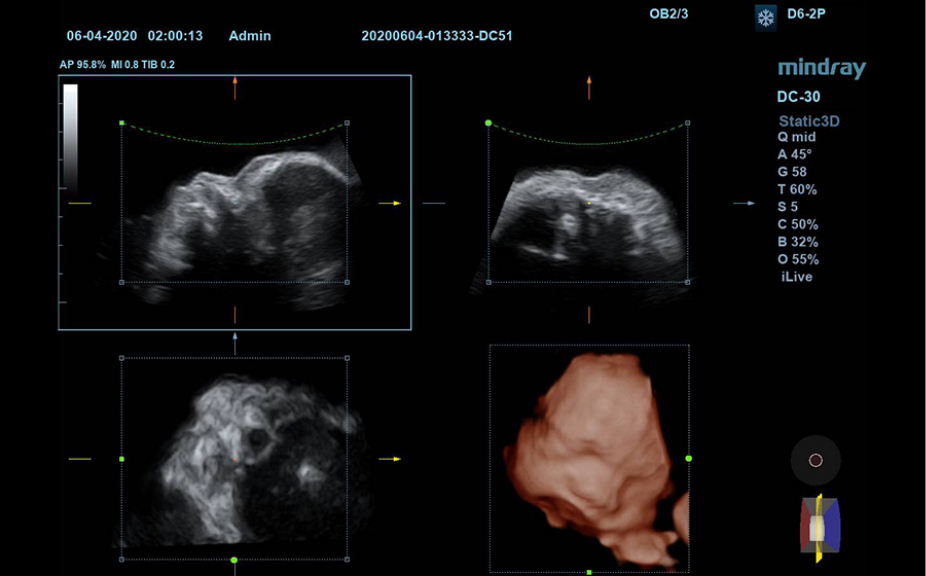

Klinik G?rĂŒntĂŒler